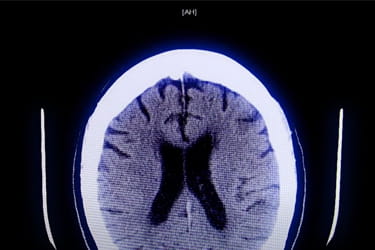

You could save a life from a stroke! Learn how to act F.A.S.T. and see warning signs.